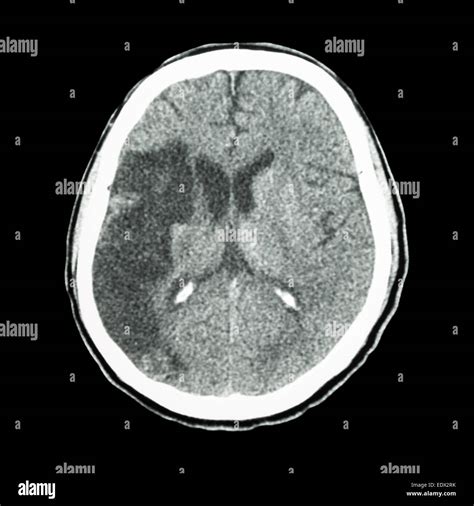

Computed Tomography (CT) scans are essential in the diagnosis of ischemic stroke. An Ischemic Stroke CT scan can quickly and accurately detect the presence of a stroke, differentiate it from other conditions, and guide treatment decisions. The scan uses X-rays to create detailed images of the brain, which can reveal:

• Non-contrast CT (NCCT): This is the most basic type of CT scan and is often the first test performed. It provides a clear view of the brain structures and can detect early signs of ischemia, such as the “dense artery sign,” which indicates a blood clot.

Interpreting the results of an Ischemic Stroke CT scan requires expertise and experience. Radiologists and neurologists work together to analyze the images and make a diagnosis. Key findings that may be observed include:

• Early ischemic changes: These can appear as areas of low density (hypodensity) in the brain tissue, indicating reduced blood flow.

• Hyperdense artery sign: This is a bright appearance of an artery on a non-contrast CT scan, suggesting the presence of a blood clot.

• Mass effect: Swelling or compression of brain tissue due to the stroke, which can be seen as a shift in the midline structures of the brain.

• Case 1: Early Detection: A 65-year-old patient presented with sudden weakness on the left side of the body and difficulty speaking. An Ischemic Stroke CT scan revealed a blood clot in the right middle cerebral artery. Thrombolytic therapy was administered within the critical time window, leading to a full recovery.

• Case 2: Complex Diagnosis: A 50-year-old patient with a history of atrial fibrillation experienced a sudden onset of vision problems and dizziness. A CT scan showed early ischemic changes in the brainstem. Further imaging with CTA and CTP confirmed the presence of a blood clot and guided the decision for mechanical thrombectomy.